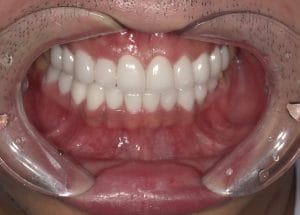

メジャーリーグでも活躍した元プロ野球選手の山口俊さんのセラミック治療を担当いたしました。

「他院で治療を受けたセラミックが欠けた」というのが主訴でしたが、よく診察するとセラミック欠けただけではなく、被せ物がしっかりと合っていないことが原因で歯茎の腫れがあり、歯石や汚れもつきやすい状態でした。また、歯列も若干歪んでいたので、この機会に全て治療いたしました。

治療後は透明感のある白さで、綺麗な歯並びになりました。また、セラミックをきちんと綺麗に削って適合よくセットしたことにより、歯茎の腫れも改善しました。

セラミックを入れた所の歯茎が腫れていて悩まれてる方はぜひご相談ください。

綺麗に削って適合よくセラミックをしてあげれば必ず改善します。